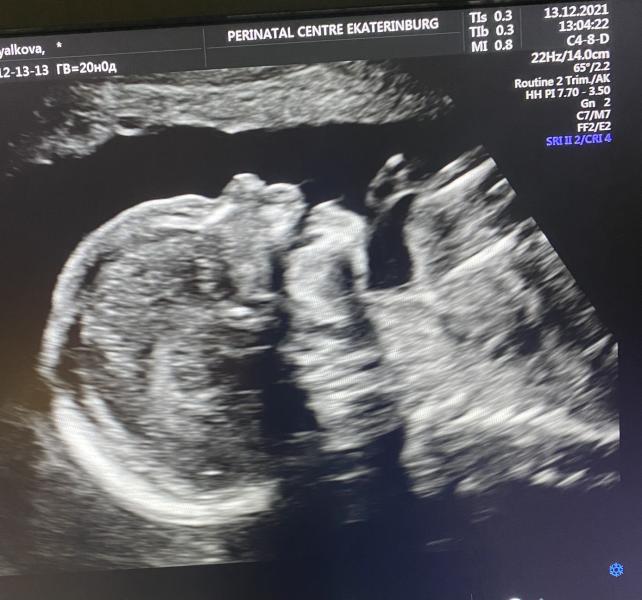

Вот и наш «экватор», ровно 20 недель! 🤰🏼Второй скрининг прошёл хорошо. Чутка короткие ручки и ножки, не в кого моделькой быть)) Девочка! 👧У нас будет маленькая крошка малышка! 👨👩👧Пока ни у меня не у мужа нет эмоций радости, главное малышка здоровая растёт! Тьфу тьфу тьфу! Думаю, что наши искренние родительские эмоции и чувства проснутся при рождении принцессы) Мамы наши уже распланировали кто шьёт а кто вяжет вещи девочке, так это всё мило🥰